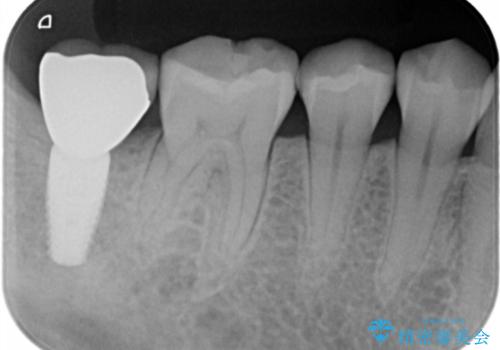

- フロスをすると引っかかる、食べ物がよく詰まるとのことで来院。

精査したところ詰め物が欠けており、物が挟まりやすく不潔になっていました。

また、小さめですが、虫歯になっていました。

そのままだといくら歯磨きを頑張っても虫歯が進行してしまいやすい状態となっていたため治療を勧めました。

虫歯を除去し、白くて目立たないセラミックインレーによる修復を行いました。

セラミックインレーの装着によりフロスが引っかからなくなりました。また、食べ物も詰まらなくなり、とても満足していただきました。